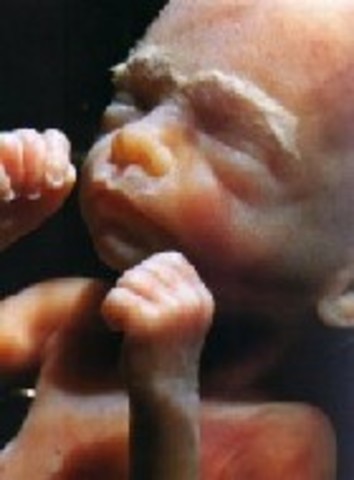

• Week 9: Fingers and Toes Form

Week 9: Fingers and Toes Form

Many more body parts are forming such as the tongue, the bones, eyelids, etc. The fingers and toes are the most defined. The baby is developing in a little bag of fluid which it is swimming around in.

• Week 10: Embryo is Now a Fetus

Week 10: Embryo is Now a Fetus

The embryo is now called a fetus until birth. The fetus is the size of a small strawberry. The fingerprints are becoming evident in the skin and the nipples and hair follicles are forming as well.